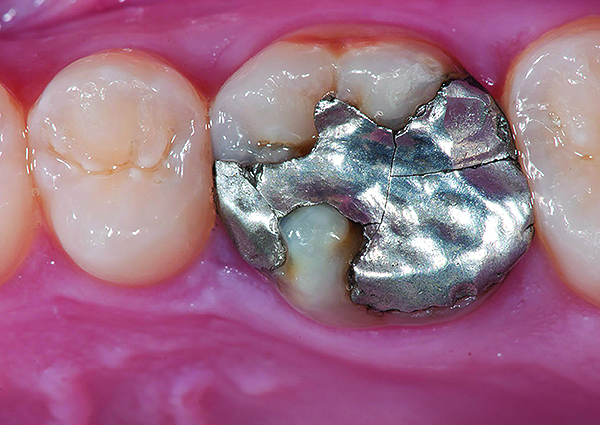

Fig 9. Preoperative view (Fig 9), preparation with composite block-out restoration (Fig 10), and final cementation of CL-IIb material (Fig 11) (final ceramic contour and stain by Steve Lee, CDT, MDC).

Figure 9

Fig 10. Preoperative view (Fig 9), preparation with composite block-out restoration (Fig 10), and final cementation of CL-IIb material (Fig 11) (final ceramic contour and stain by Steve Lee, CDT, MDC).

Figure 10

Fig 11. Preoperative view (Fig 9), preparation with composite block-out restoration (Fig 10), and final cementation of CL-IIb material (Fig 11) (final ceramic contour and stain by Steve Lee, CDT, MDC).

Figure 11